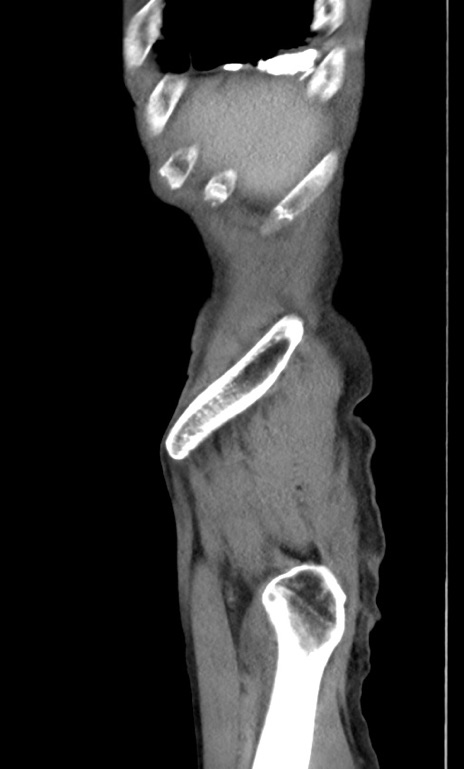

横断像